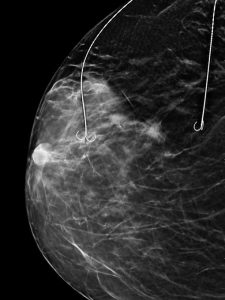

În cadrul SCJU Constanța – Secția Chirurgie 1, sub coordonarea Prof. Univ. Dr. Răzvan Popescu, a fost realizată în premieră o intervenție de conservare a sânului în cazul unei paciente cu trei leziuni maligne, prin tehnica Bracketing cu două harpoane.

-Dr. Alexandru Gavrilă – medic primar radiologie și imagistică medicală, cu competență în senologie